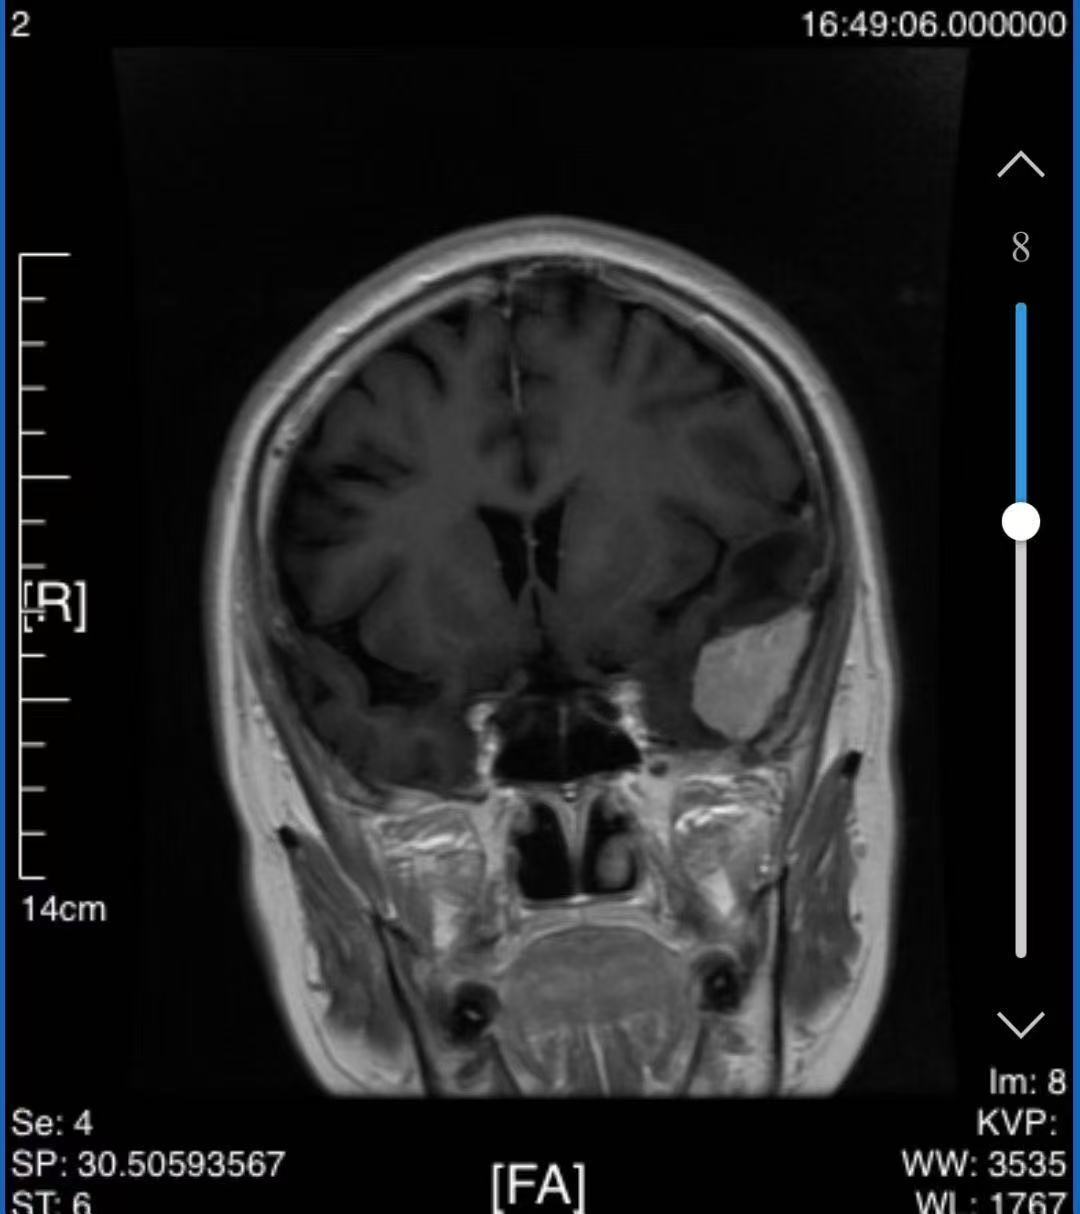

患者是一位65岁的女性,因长期头痛、右侧肢体乏力就医,检查发现左侧颞叶有一个直径约3厘米的脑膜瘤。肿瘤位置深、紧贴重要脑功能区,手术难度和风险都很高。托克逊县人民医院神经医学科团队在肖虎主任的组织下,与谢竹青主任进行了多次远程会诊。为保障手术顺利,谢竹青主任决定亲赴新疆指导手术。

抵达托克逊后,谢竹青主任立即参与术前评估,结合影像资料与患者情况,确认肿瘤已累及颅底,属于高难度颅底肿瘤手术。他与当地团队共同制定了详细的手术方案和应急预案,并就术中如何保护神经功能、术后如何康复等细节进行了充分沟通。